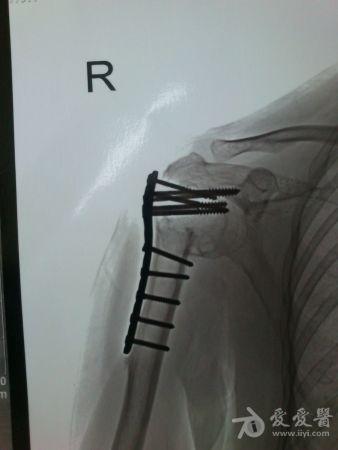

病史特点及病情摘要:1、患者女性,51岁。2、患者自诉入院前1年余因右肱骨外科颈骨折在外院行切开复位内固定术,术后右肩关节疼痛、活动受限,一直未予处理,今为明确诊治入院。患者精神、食欲、睡眠尚可。3、既往史、个人史、家族史无特殊。4、入院查体:生命征平稳,心肺腹检查未见异常,NS(-)。专科情况:右上臂近端内侧见一约15cm手术切口疤痕,愈合佳,右肩关节能外展20度,前屈、后伸及旋前、旋后功能障碍,余关节活动好。舌质红,苔薄白,脉实。5、辅助检查:右肩关节正侧位片:右肱骨外科颈骨折内固定术后再骨折伴右肩关节脱位。

诊疗计划:????前两张片是院外术前,中间两张是院外术后,后两张是在我院照。 术前

院外术后

同意楼主观点,患者第一次手术复位欠佳,但可勉强接受。但钉子穿出,是手术后肩关节疼痛的主要原因,现在看骨折已愈合,头无明显头坏死迹象,只需取出内固定,麻醉下活动肩关节,使肩关节活动度改善,术后加强功能锻炼,应该恢复不错。